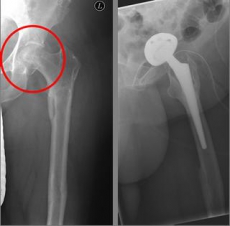

Picture: In this case, there was already a wear of the hip joint and the affected patient was relatively young, so that a cement-free total endoprosthesis (TEP) of the hip was selected for the treatment of the femoral neck fracture. Here, in addition to the femoral head, the acetabular cup was replaced by an implant.